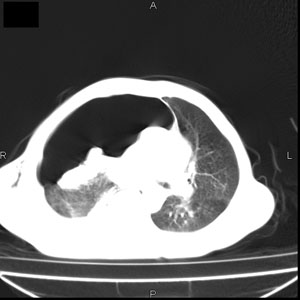

患者男,77岁,于3日前从树上摔下,头部查ct示蛛血,硬膜下出血,上腹部ct未见明显异常,右侧胸腔积液,左侧如常。肺部拍片示右侧肋骨多发骨折住院后今日来查肺部ct,我看到的是1。右侧胸腔血气胸并右肺上叶,中叶压缩性肺不张,2。右肺下叶肺挫伤并多发肋骨骨折,肌内及皮下积气3。左侧少量胸腔积液,我想请教的是3天前左侧胸腔里没有积液今天怎么出现了呢,是什么原因呢?请讨论。

有肺挫裂伤,有渗出,

回复楼主   左侧液气胸,液体来源1、肯定有血液成分,多少不一定。2、胸膜腔渗液,由于肺压缩、活动度下降,肯定胸膜吸收有问题,导致积液增多。

因为3天前病人刚摔的时候,左侧胸腔受伤不严重,故而当时没有胸腔积液,但病人受到这么大的伤害,胸膜腔内的液体动态平衡肯定会受到影响,所以过一段时间后才出现胸腔积液。

1、外伤出血需要一定的时间

2、气胸存在时间长了,产生的胸膜渗液

考虑外伤性迟发性胸腔积液。

右侧液气胸,胸膜创伤、肺组织挫伤,渗出属正常反应。